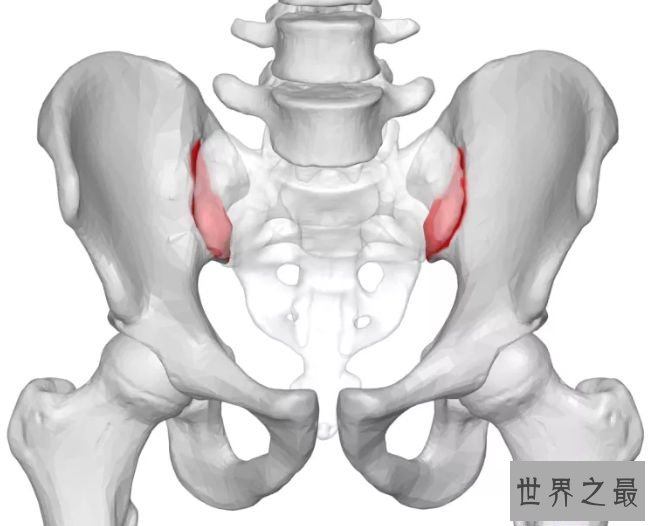

3.女性生孩子时骨盆骨会变化

女性的身材在怀孕时期变化很大,骨盆关节有一些骨骼顺应影响松弛。一种叫做松弛素的激素在女性的子宫颈和肌肉、韧带和骨盆衔接处都十分重要,它们会让女性在分娩时期骨盆关节变得更有弹性。